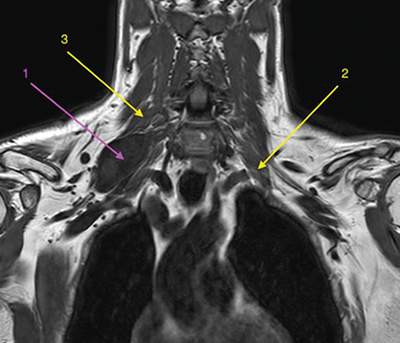

Figura 1